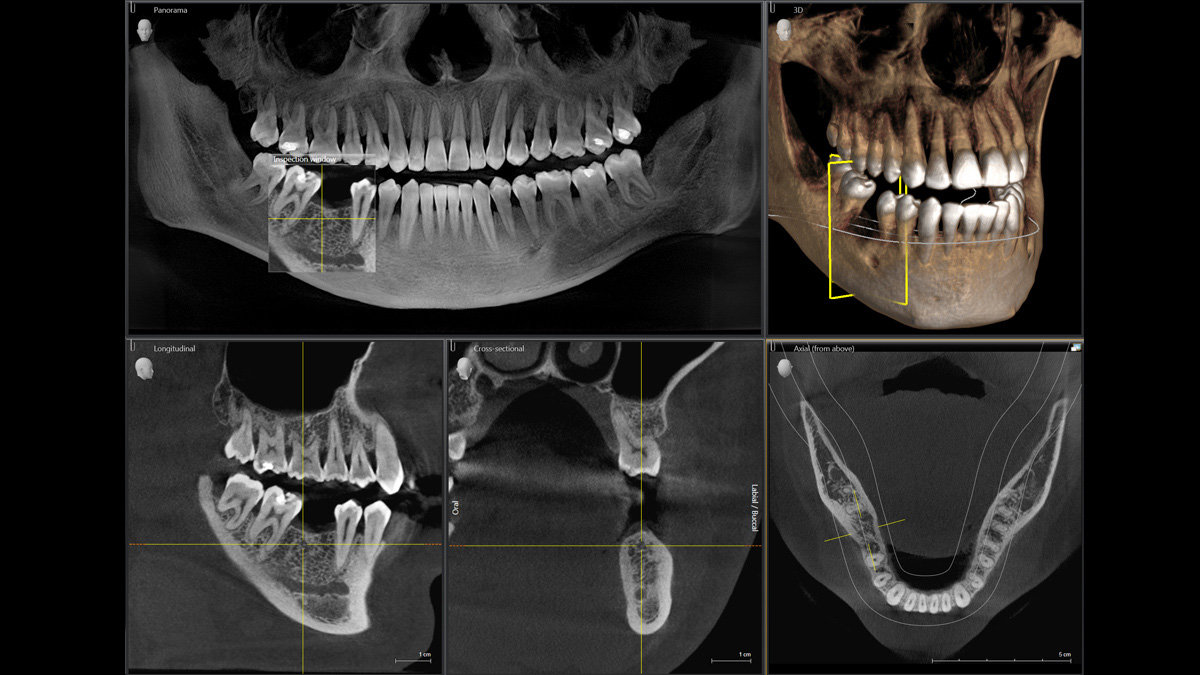

With the 3D Intelligent Low Dose mode, you get 3D images in the dose range of a 2D X-ray. In HD mode (up to 1,400) individual images are captured during a single rotation and converted into a 3D volume with up to 80 μm for low-noise images in high resolution.

A broad range of volume sizes to support your various diagnostic and clinical needs from Ø 5 x 5.5 cm to Ø 11 x 10 cm